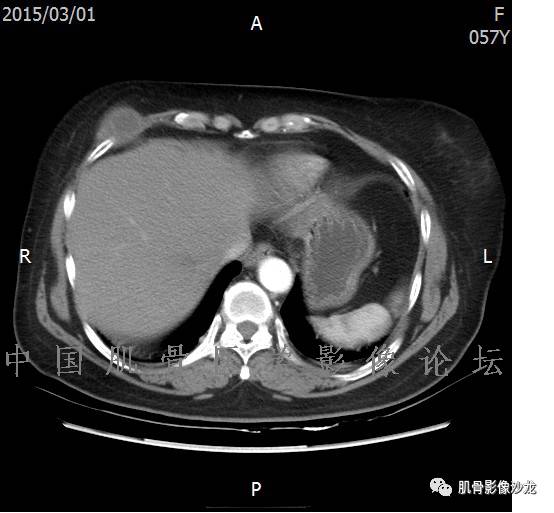

患者于2月前无明显诱因下出现腰骶部疼痛,夜间为重,逐渐加重伴左下肢麻木、疼痛,并有行走活动受限,在我院就诊,摄腰椎及骶髂部CT提示:腰椎骨质退变,腰3-4、4-5椎间盘膨出,骶髂关节炎。自用非甾体抗炎药无好转,再次来院就诊,门诊拟“骶髂关节炎”收住我科。病程无间歇性跛行,大小便正常。

专科检查:神清,脊柱无侧弯后凸畸形,椎体各节段无压、叩痛,双侧棘突旁无压痛,双侧骶髂关节压痛明显,左下肢放射痛,浅感觉较健侧减退,腰椎前屈后伸活动受限,膝、跟腱反射正常。

辅助检查:腰椎及骶髂部CT提示:腰椎骨质退变,腰3-4、4-5椎间盘膨出,骶髂关节炎。

雪舞 :第二例,位于骶骨,有骨质破坏并有软组织肿块,软组织肿块边界清

雪舞 :第二例挺难的,骨质破坏是溶骨性的,局部皮质中断,软组织肿块外缘光滑